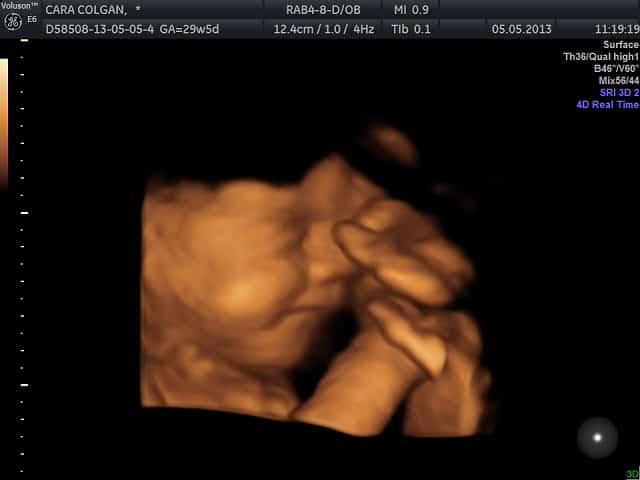

Dalam kajian dilakukan pengkaji daripada New Zealand pada 2005 menunjukkan video ultrabunyi bayi yang dianggap sedang menangis.

Beberapa pecahan dilakukan, melibatkan gerakan badan dan pernafasan bagi mengesahkan bayi dalam kandungan itu menangis.

Dalam kajian lain pada 2011 yang memfokuskan tentang ekspresi wajah si manja sebelum kelahiran sebagai penunjuk utama tindak balas tangisan.

Ini bermakna semasa membuat ujian ultrabunyi, anda mungkin melihat ekspresi wajah si comel berkerut, tetapi tiada bunyi yang didengar.